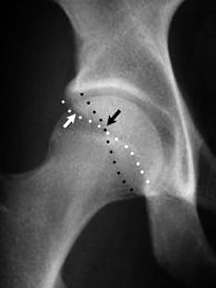

One of the subtle anatomic abnormalities linked with femoroacetabular impingement is acetabular retroversion. It is now recognized that this anatomic abnormality results in cartilage degeneration secondary to femoroacetabular impingement, resulting in OA of the hip.3-4 Retroversion of the acetabulum is described as an abnormal morphologic feature involving a posteriorly oriented cranial acetabular opening in the sagittal plane, which is seen as the crossover sign (COS) on standard radiographs. The COS as seen on standard AP radiographs is indicates the presence of acetabular retroversion. Jamali5 confirmed that COS indicates retroversion of the acetabulum, which primarily affects the cranial portion of the acetabulum.

Figure 2: Edge of anterior wall (white arrow) is medial to the edge of posterior wall (black arrow) in inferior segment of the hip, but in the superior segment, this relationship reverses. This leads to the "crossover sign."